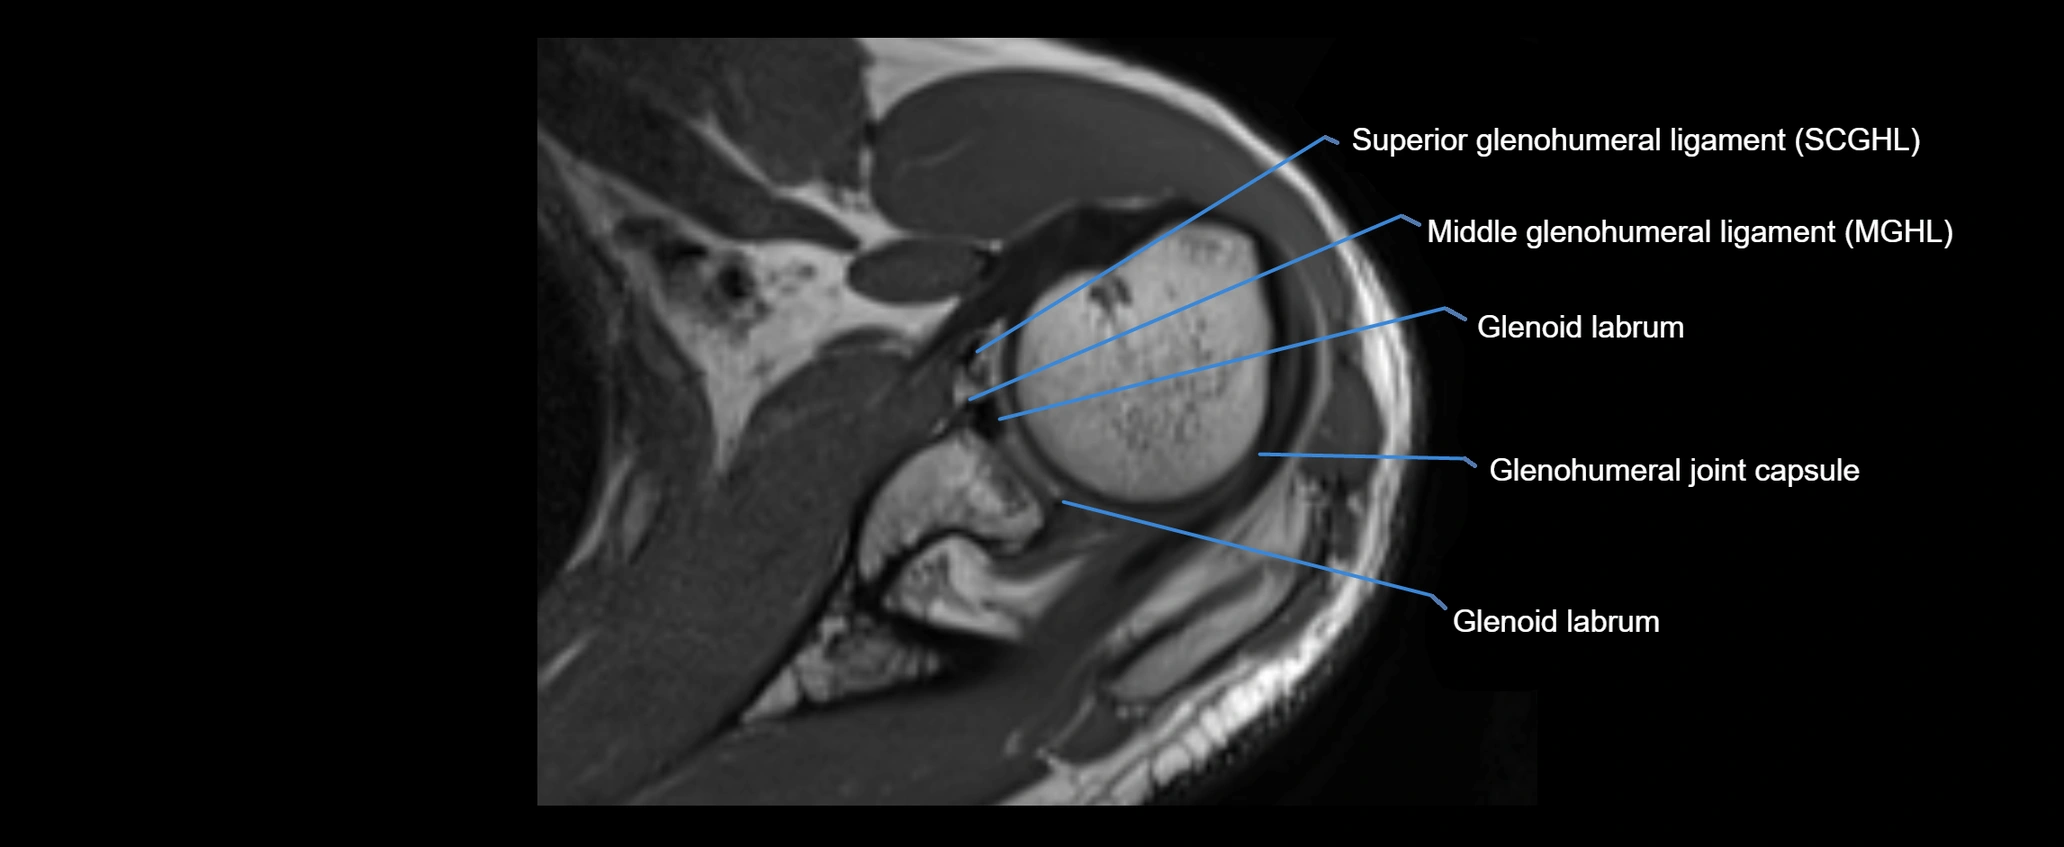

MRI Appearance

• T1-weighted images:

• Normal ligament: Low signal (dark linear band) spanning acromion to clavicle.

• T2-weighted images:

• Normal ligament: Low signal, homogeneous.

• Proton Density Fat-Saturated (PD FS):

• Normal ligament: Low signal, uniform thickness.

MRI images

image